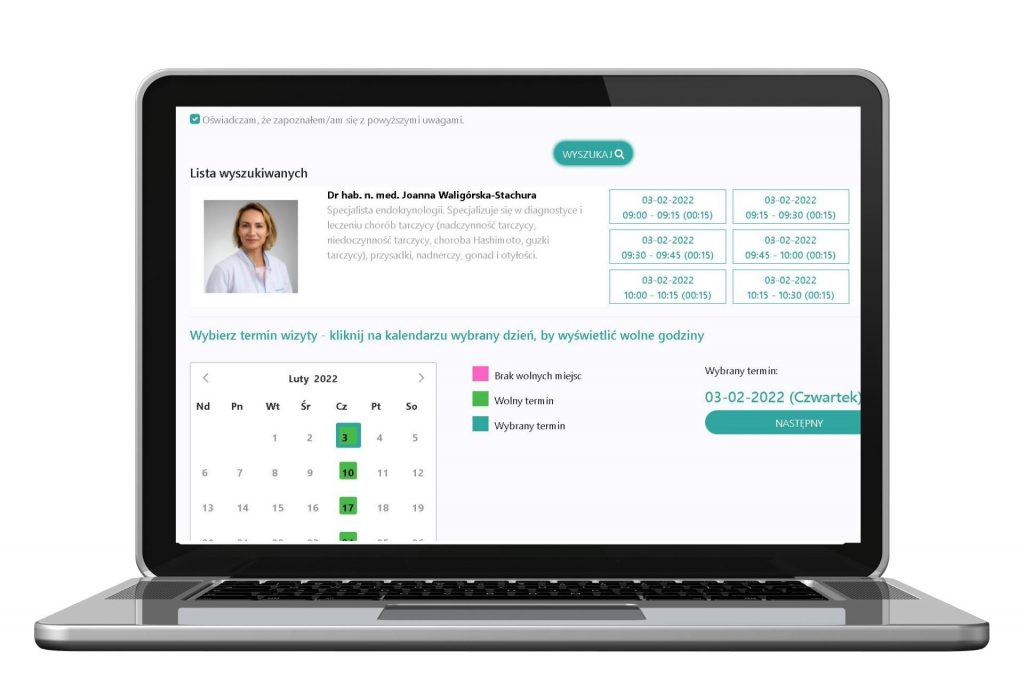

W neoMedica realizujemy projekt dofinansowany z Funduszy Europejskich Zakup urządzeń i oprogramowania celem wdrażania innowacyjnych usług medycznych przez centrum medyczne w Poznaniu w ramach WRPO na lata 2014-2020.

Planowane efekty projektu:

- Wzrost zatrudnienia we wspieranych przedsiębiorstwach: 1 EPC

- Liczba wprowadzonych innowacji produktowych: 2

- Liczba wprowadzonych innowacji procesowych: 2

- Liczba wprowadzonych innowacji nietechnologicznych: 2